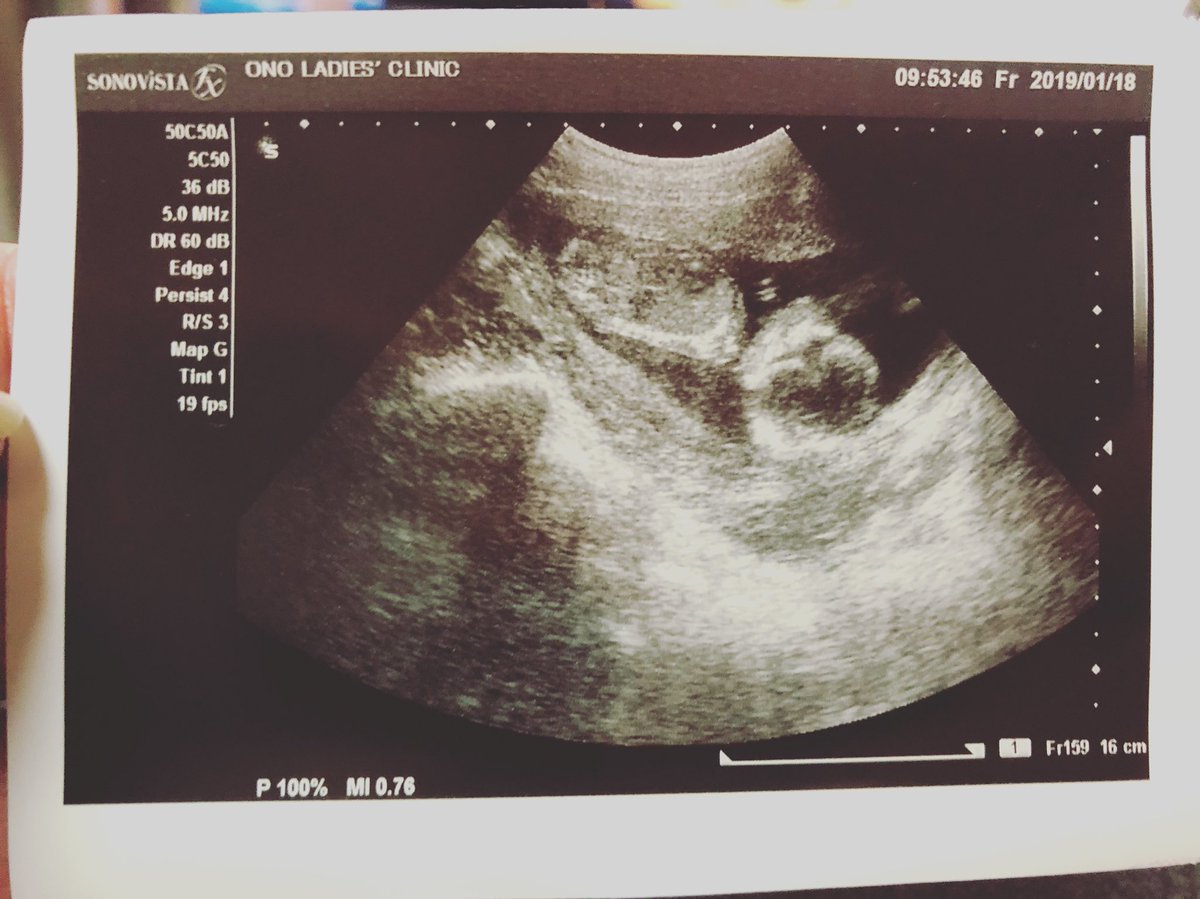

妊娠15週 3 6日 のエコー写真 体験談

妊娠15週目 15w0d 6d のエコー写真とエピソード 妊娠4ヶ月 Cozre コズレ 子育てマガジン

妊娠15週目のエコー写真とママの気持ち 胎児 ママの状態は 注意点は ママズアップ